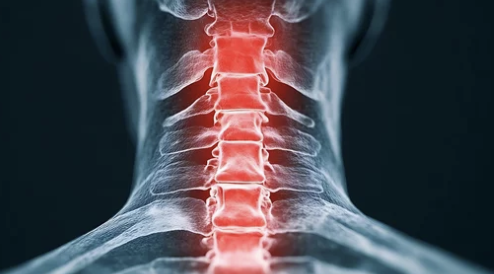

1. 목디스크란 무엇인가?

목디스크의 정의

목디스크(경추 추간판 탈출증)는 목뼈 사이에 있는 디스크(추간판)가 탈출하거나 찢어져 신경을 압박하는 상태를 말합니다. 이로 인해 통증, 저림, 움직임 제한 등이 발생합니다.